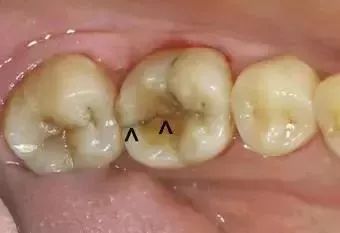

来自山西的吴医生分享了他保留的几张可乐牙病例照,我们一块来“欣赏”一下。

被碳酸腐蚀的牙齿